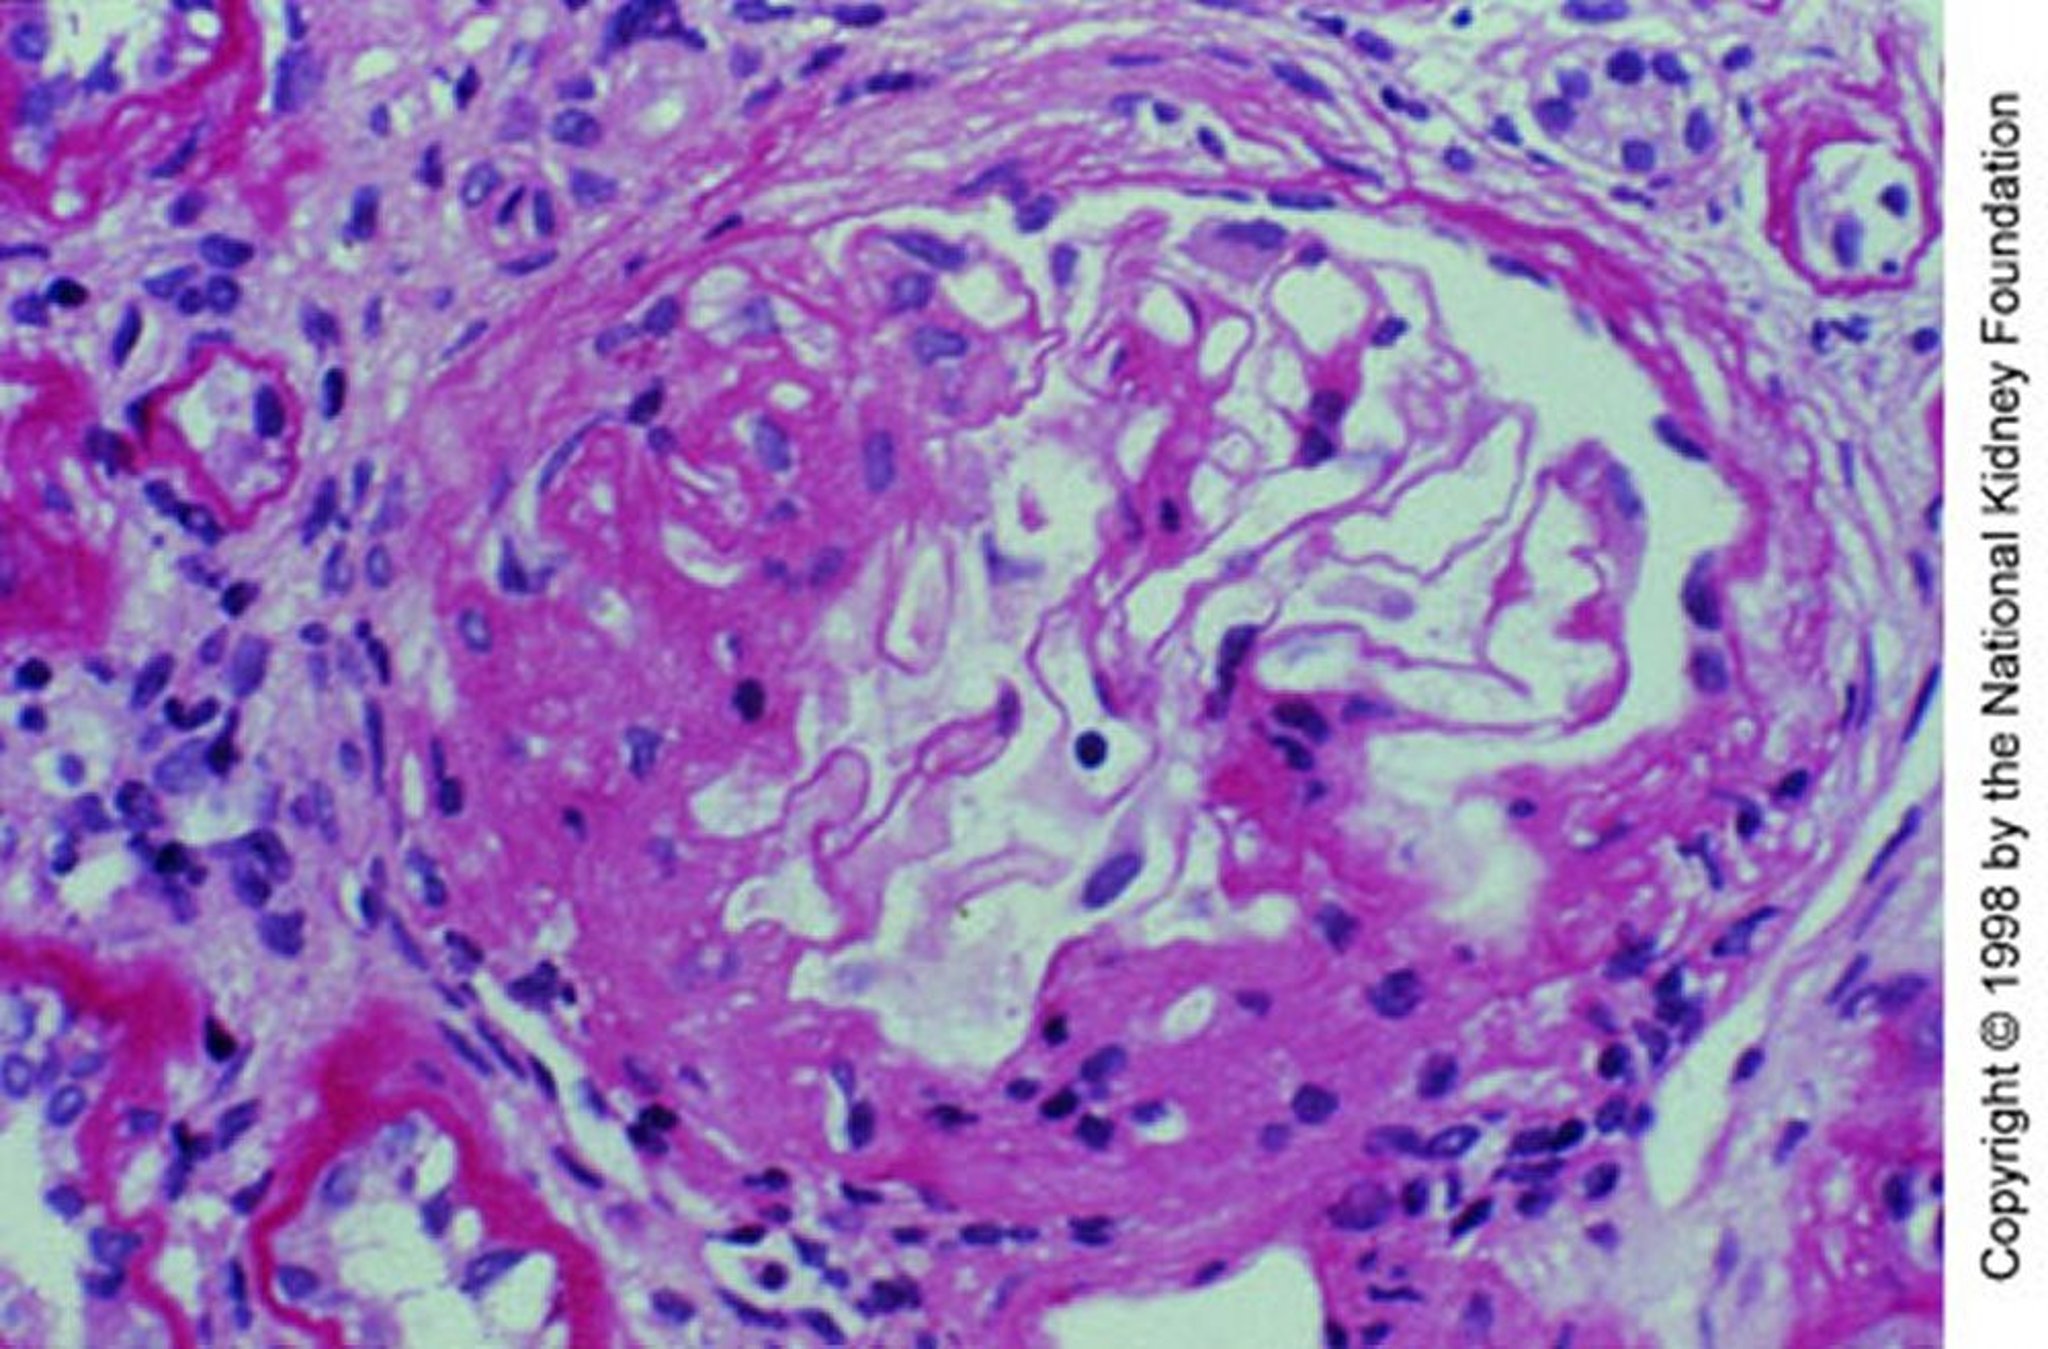

Image provided by Agnes Fogo, MD, and the American Journal of Kidney Diseases' Atlas of Renal Pathology (see www.ajkd.org).

Биопсия почек показывает гранулярные включения IgA и комплемента (СЗ) при иммунофлюоресцентном окрашивании в расширенном мезангии с очагами сегментарных пролиферативных или некротических изменений. Важно отметить, что мезангиальные отложения IgA неспецифичны и встречаются также и при многих других заболеваниях, включая иммуноглобулин А-васкулит, цирроз печени, воспалительные заболевания кишечника, целиакию, псориаз, ВИЧ-инфекцию, рак легких и некоторые системные ревматические заболевания.